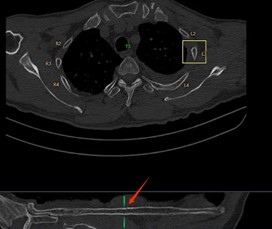

在一些大型醫(yī)院和醫(yī)療研究機(jī)構(gòu),已經(jīng)開(kāi)始嘗試這種協(xié)作模式。例如,在胸部CT肺結(jié)節(jié)以及肋骨骨折的影像診斷中,AI 首先對(duì)影像進(jìn)行分析,標(biāo)記出可能的異常區(qū)域,醫(yī)生再對(duì)這些區(qū)域進(jìn)行詳細(xì)觀察和診斷。通過(guò)這種協(xié)作,不僅提高了診斷效率,還提升了診斷的準(zhǔn)確性。